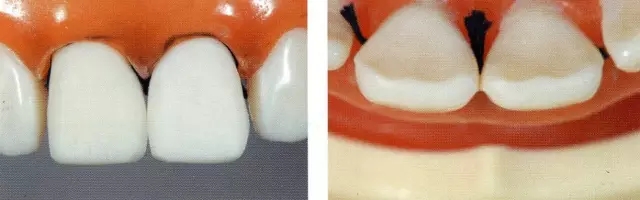

圖6 鄰接面和切緣的預(yù)備。避免傷到牙齦,要做排齦。如果遇到插不進(jìn)鄰接面的情況,可以在鄰接面預(yù)備好后再進(jìn)行插入。注意預(yù)備時(shí)不要磨到鄰接牙,把硅橡膠模型用在切緣上,這樣可以很好把握切削量。

圖7 確認(rèn)唇側(cè)切緣處的切削量。用硅橡膠模型可以確認(rèn)唇側(cè)面的切削量(約0.8mm)。鄰接面預(yù)備深度是隨著鄰接面接觸點(diǎn)有無、頰舌寬度、鼓形空隙的大小而變化的。

圖8 確認(rèn)唇側(cè)中央處的預(yù)備量。用硅橡膠印模確認(rèn)預(yù)備量。(約0.8mm)

圖9唇側(cè)牙頸部預(yù)備量的確認(rèn)。用硅橡膠印模確認(rèn)預(yù)備量。(約0.5mm)

圖10 完成牙體預(yù)備。以讓應(yīng)力分散型對(duì)線角、點(diǎn)角進(jìn)行了圓滑處理。